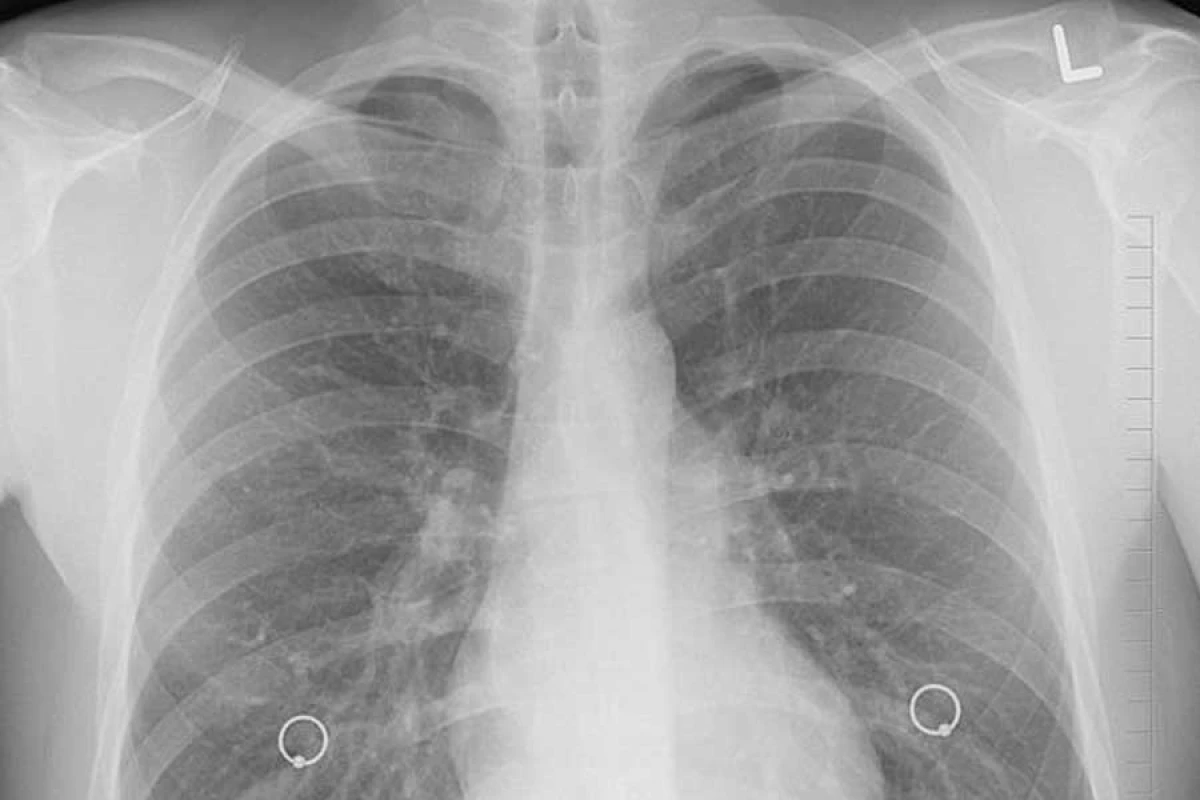

Як з'ясувалося в ході експериментів, легені мишей виробляють понад 50% тромбоцитів всього організму. В легенях мишей вченим вдалося також виявити стовбурові клітини крові, які мають здатність відновлюватися. Раніше фахівці вважали, що стовбурові клітини містяться виключно в кістковому мозку.

"Ця знахідка виразно пропонує більш складну концепцію легенів - це органи не тільки для дихання, вони є учасником формування клітин крові. Те, що ми спостерігали у мишей, дозволяє припустити, що легені можуть відігравати ключову роль у формуванні крові в організмі людини", - говорить один з дослідників, Марк Р. Луні.